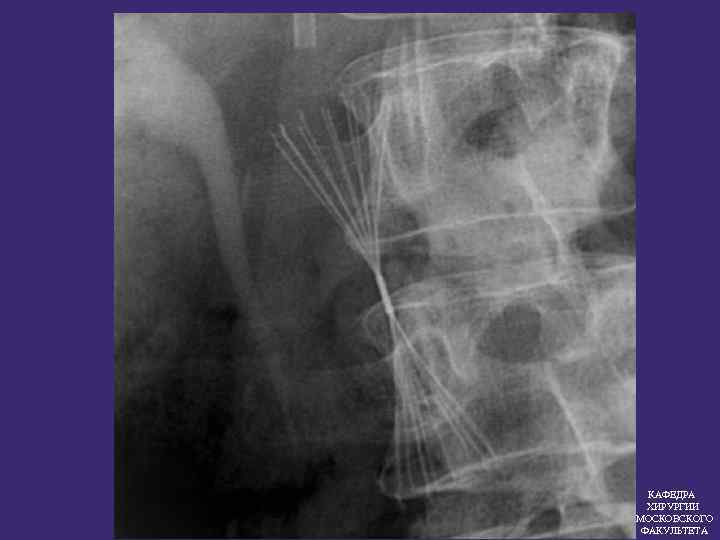

ПРОТИВОЭМБОЛИЧЕСКИЕ КАВАФИЛЬТРЫ Эффективность кава фильтров 97, 5% КАФЕДРА ХИРУРГИИ МОСКОВСКОГО ФАКУЛЬТЕТА

ПОКАЗАНИЯ К ИМПЛАНТАЦИИ КАВА-ФИЛЬТРА 1. Флотирующие тромбы в системе НПВ 2. Массивная ТЭЛА Повторные ТЭЛА без установленного источника 3. КАФЕДРА ХИРУРГИИ МОСКОВСКОГО ФАКУЛЬТЕТА